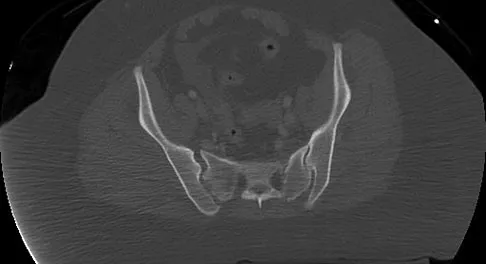

Figure 11 shows the radiograph of a 26-year-old man with type I diabetes mellitus who was struck by a motor vehicle. What is the most common complication associated with this pelvic fracture?

Explanation

The most common complication following acetabular or pelvic ring injury is deep venous thrombosis (DVT). Without prophylaxis, rates of DVT are as high as 70% to 80%. With prophylaxis, the rates are around 10%. Infection rates in surgical repair of acetabular fractures are relatively low but a history of diabetes mellitus and a significant Morel-Lavalle lesion certainly increase the risk. However, even with these two complicating factors, the rates of infection are still lower than 10%. Sciatic nerve palsy rates from the injury alone approach 20% and iatrogenic injury is usually less than 2%. Degenerative changes to the hip following this injury approach 20% to 25%, even with an anatomic reduction. Geerts WH, Code KI, Jay RM, et al: A prospective study of venous thromboembolism after major trauma. N Engl J Med 1994;331:1601-1606.